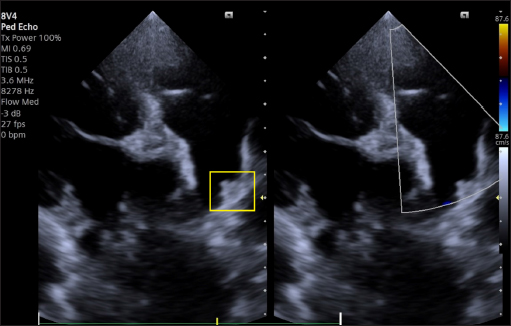

The dog was discharged, and a check-up was scheduled for 30 days. The 1-month TTE echocardiographic examination confirmed complete occlusion of the PDA, without residual shunting on Color Flow Mapping (CFM), correct positioning of the device, with complete reverse remodeling of the cardiac chambers (Fig. 8).

Fig. 8. Dual-mode transthoracic echocardiography (left cranial parasternal view optimized for duct visualization) at 30 days after surgery. The device (yellow square) is correctly positioned, and no evidence of residual shunt or pulmonary arterial obstruction is present on CFM Doppler.